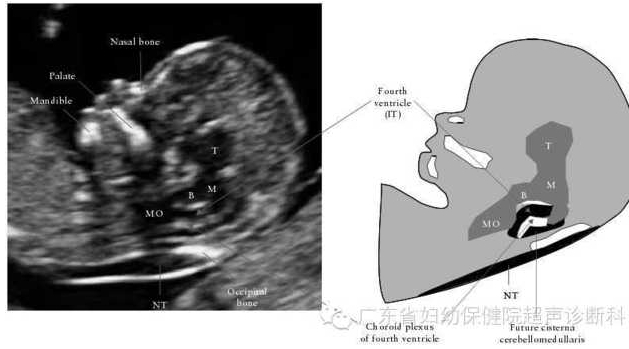

脊柱裂是胎儿常见的中枢神经管畸形之一,是由于在胚胎发育时期受某些原因影响而造成神经管不能闭合所致。脊柱裂在我国的发生率为0.274%,其中开放性脊柱裂占30.9%。尽管可以通过超声检查来诊断开放脊柱裂,但在孕14周以前由于病灶较小和常规超声检查胎儿解剖结构中缺乏可靠的颅骨和脑组织形态改变的间接征象(如“柠檬头”和“香蕉小脑”);另外,早孕期脊柱骨化未完全,超声难以直接观察脊柱的形态和排列异常等直接征象,目前筛查和诊断开放性脊柱裂胎儿大多在中晚孕期。超声在孕11~13+ 6周胎儿面部正中矢状面上测量颈项透明层(nuchal translucency,NT)已经作为筛查染色体异常的手段之一。在这个切面上,可以观察到位于脑干和脉络丛之间的第四脑室,由于第四脑室回声与颈项透明层相似,故命名为颅内透明层( intracranial translucency,IT) 。开放性脊柱裂胎儿脑组织向尾侧移位,导致第四脑室受压变小,而正常孕11~13+6周胎儿第四脑室清晰可见。本文通过几篇文献复习,与大家一起分享一个新的可能是更早期的诊断开放性脊柱裂的指标——颅内透明层(IT)。